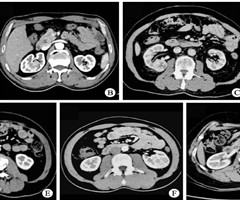

肾部分切除术中假包膜外基底静脉癌栓的发现及临床意义:8例报告及探讨

摘要:目的总结行肾部分切除术时发现假包膜外基底静脉癌栓肾癌患者的临床特点,并探讨其临床意义,以加深对肾癌伴癌栓形成机制的理解。方法回顾性分析西安交通大学第二附属医院 2023年9月—2025年7月行肾部分切除术的209例肾癌(Tla162 ...

伴肾静脉属支侵犯的肾细胞癌:诊断的挑战及机器人辅助腹腔镜下肾部分切除术短期疗效

摘要:目的探讨机器人辅助腹腔镜下肾部分切除术(RAPN)治疗伴肾静脉属支侵犯的肾细胞癌(RCC)患者的短期疗效,总结诊治该类患者的经验与手术技术要点。方法回顾性分析 2022—2024年由同一医生(有机器人手术超过1000例经验)团队实施R...